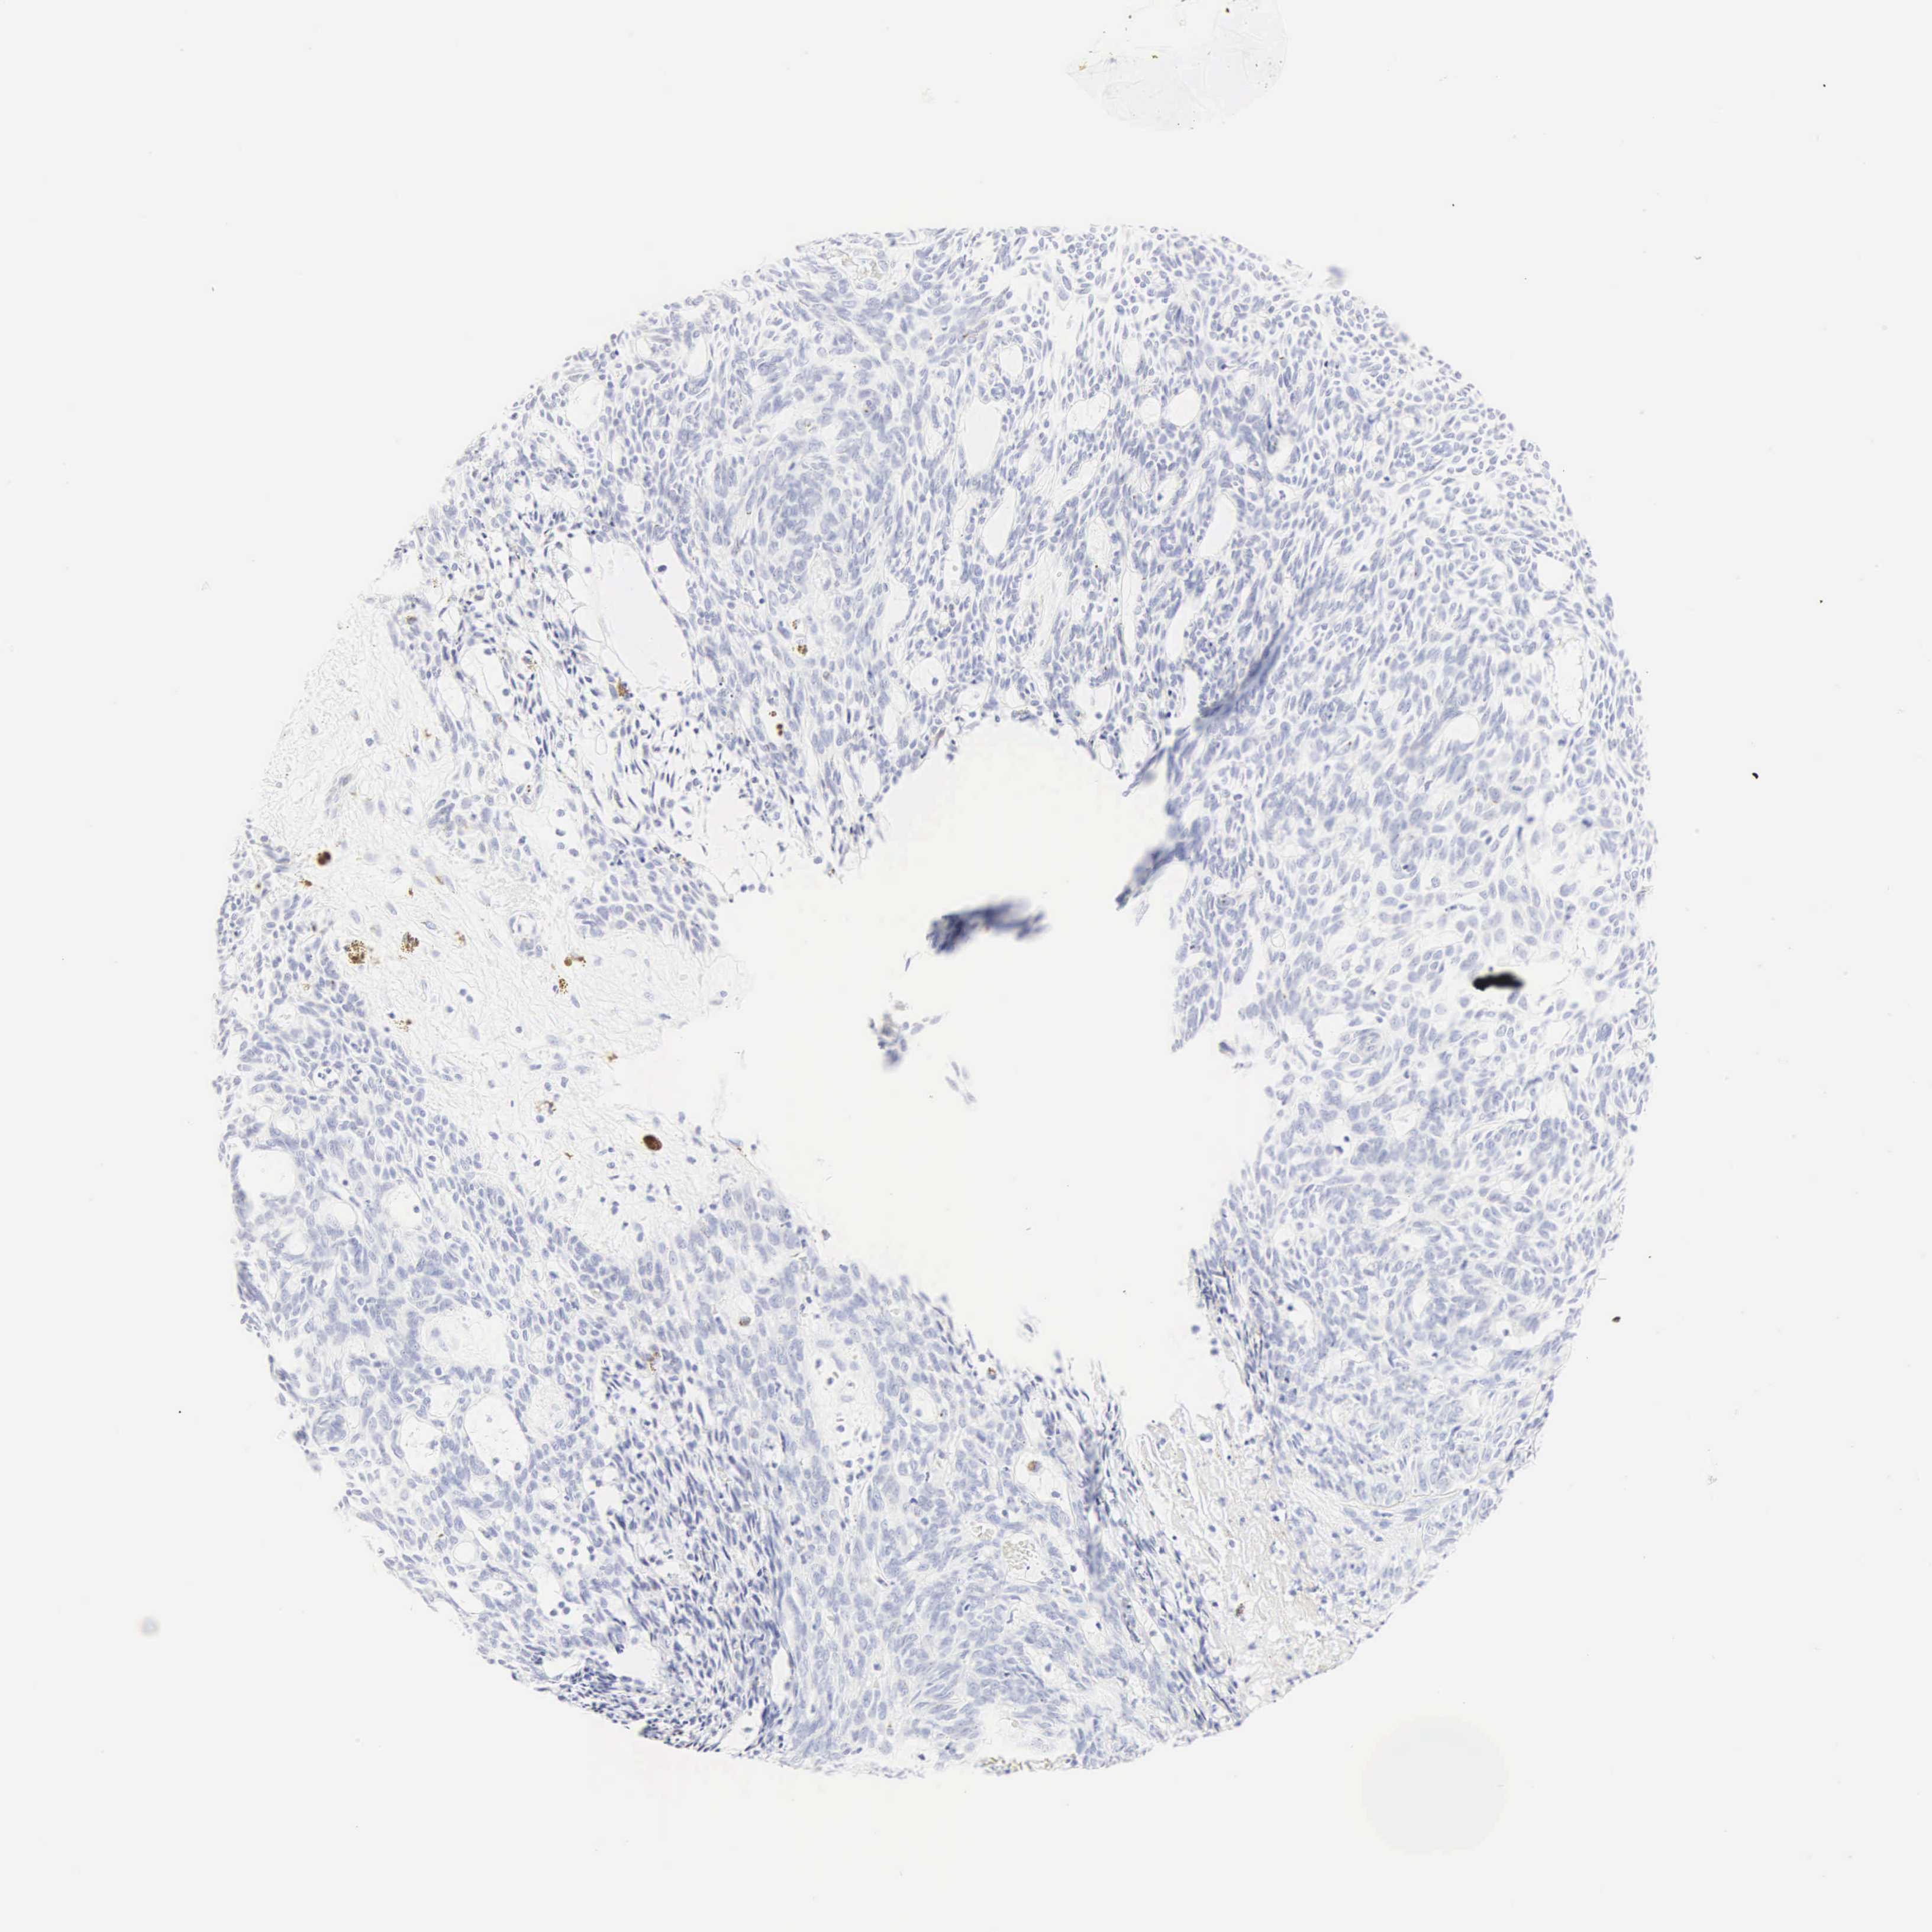

SKIN CANCER - Protein expressioni

A mouse-over function shows sample information and annotation data. Click on an image to view it in a full screen mode. Samples can be filtered based on level of antibody staining by selecting one or several of the following categories: high, medium, low and not detected. The assay and annotation is described here.

Each image is clickable and will lead to virtual microscopy that enables deeper exploration of all samples and also displays staining intensity scores, fraction scores and subcellular localization as well as patient and tissue information for each sample.

Antibody HPA038934

Squamous cell carcinoma, NOS